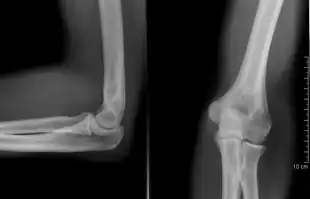

A plain radiograph of the elbow